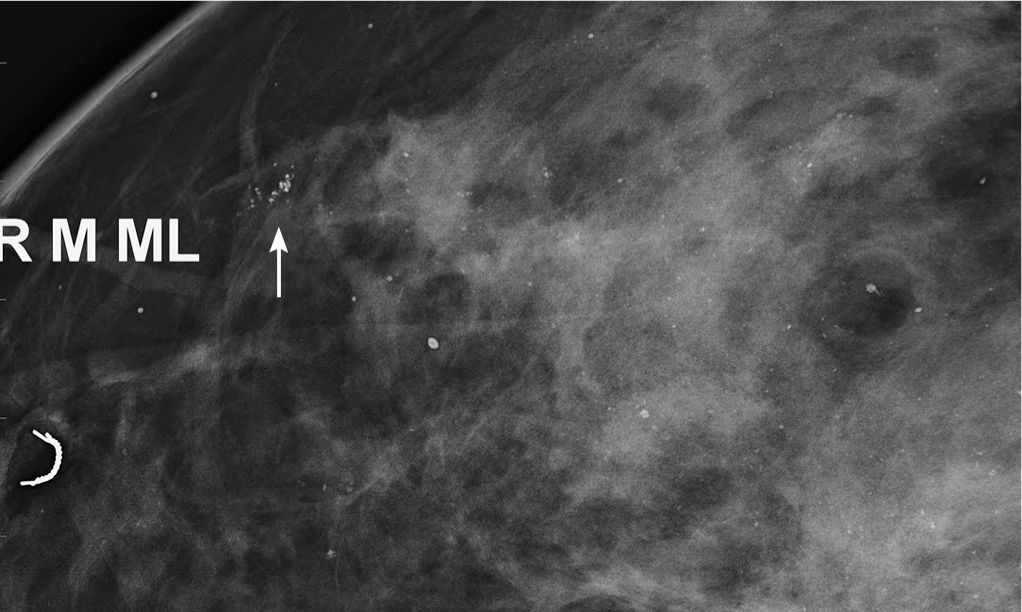

Mammographic spot magnification CC (A) and ML (B) views of the left Magnification Radiology The section on magnification (p. 162) outlined the ideal conditions. Magnification and collimation in radiography. A magnification view in mammography is performed to evaluate and count microcalcifications and its extension (as well the. The positioning of the patient (geometry) to produce an image has a direct relationship to the quality of that image. Magnification radiography is a highly specialized, not. Magnification Radiology.